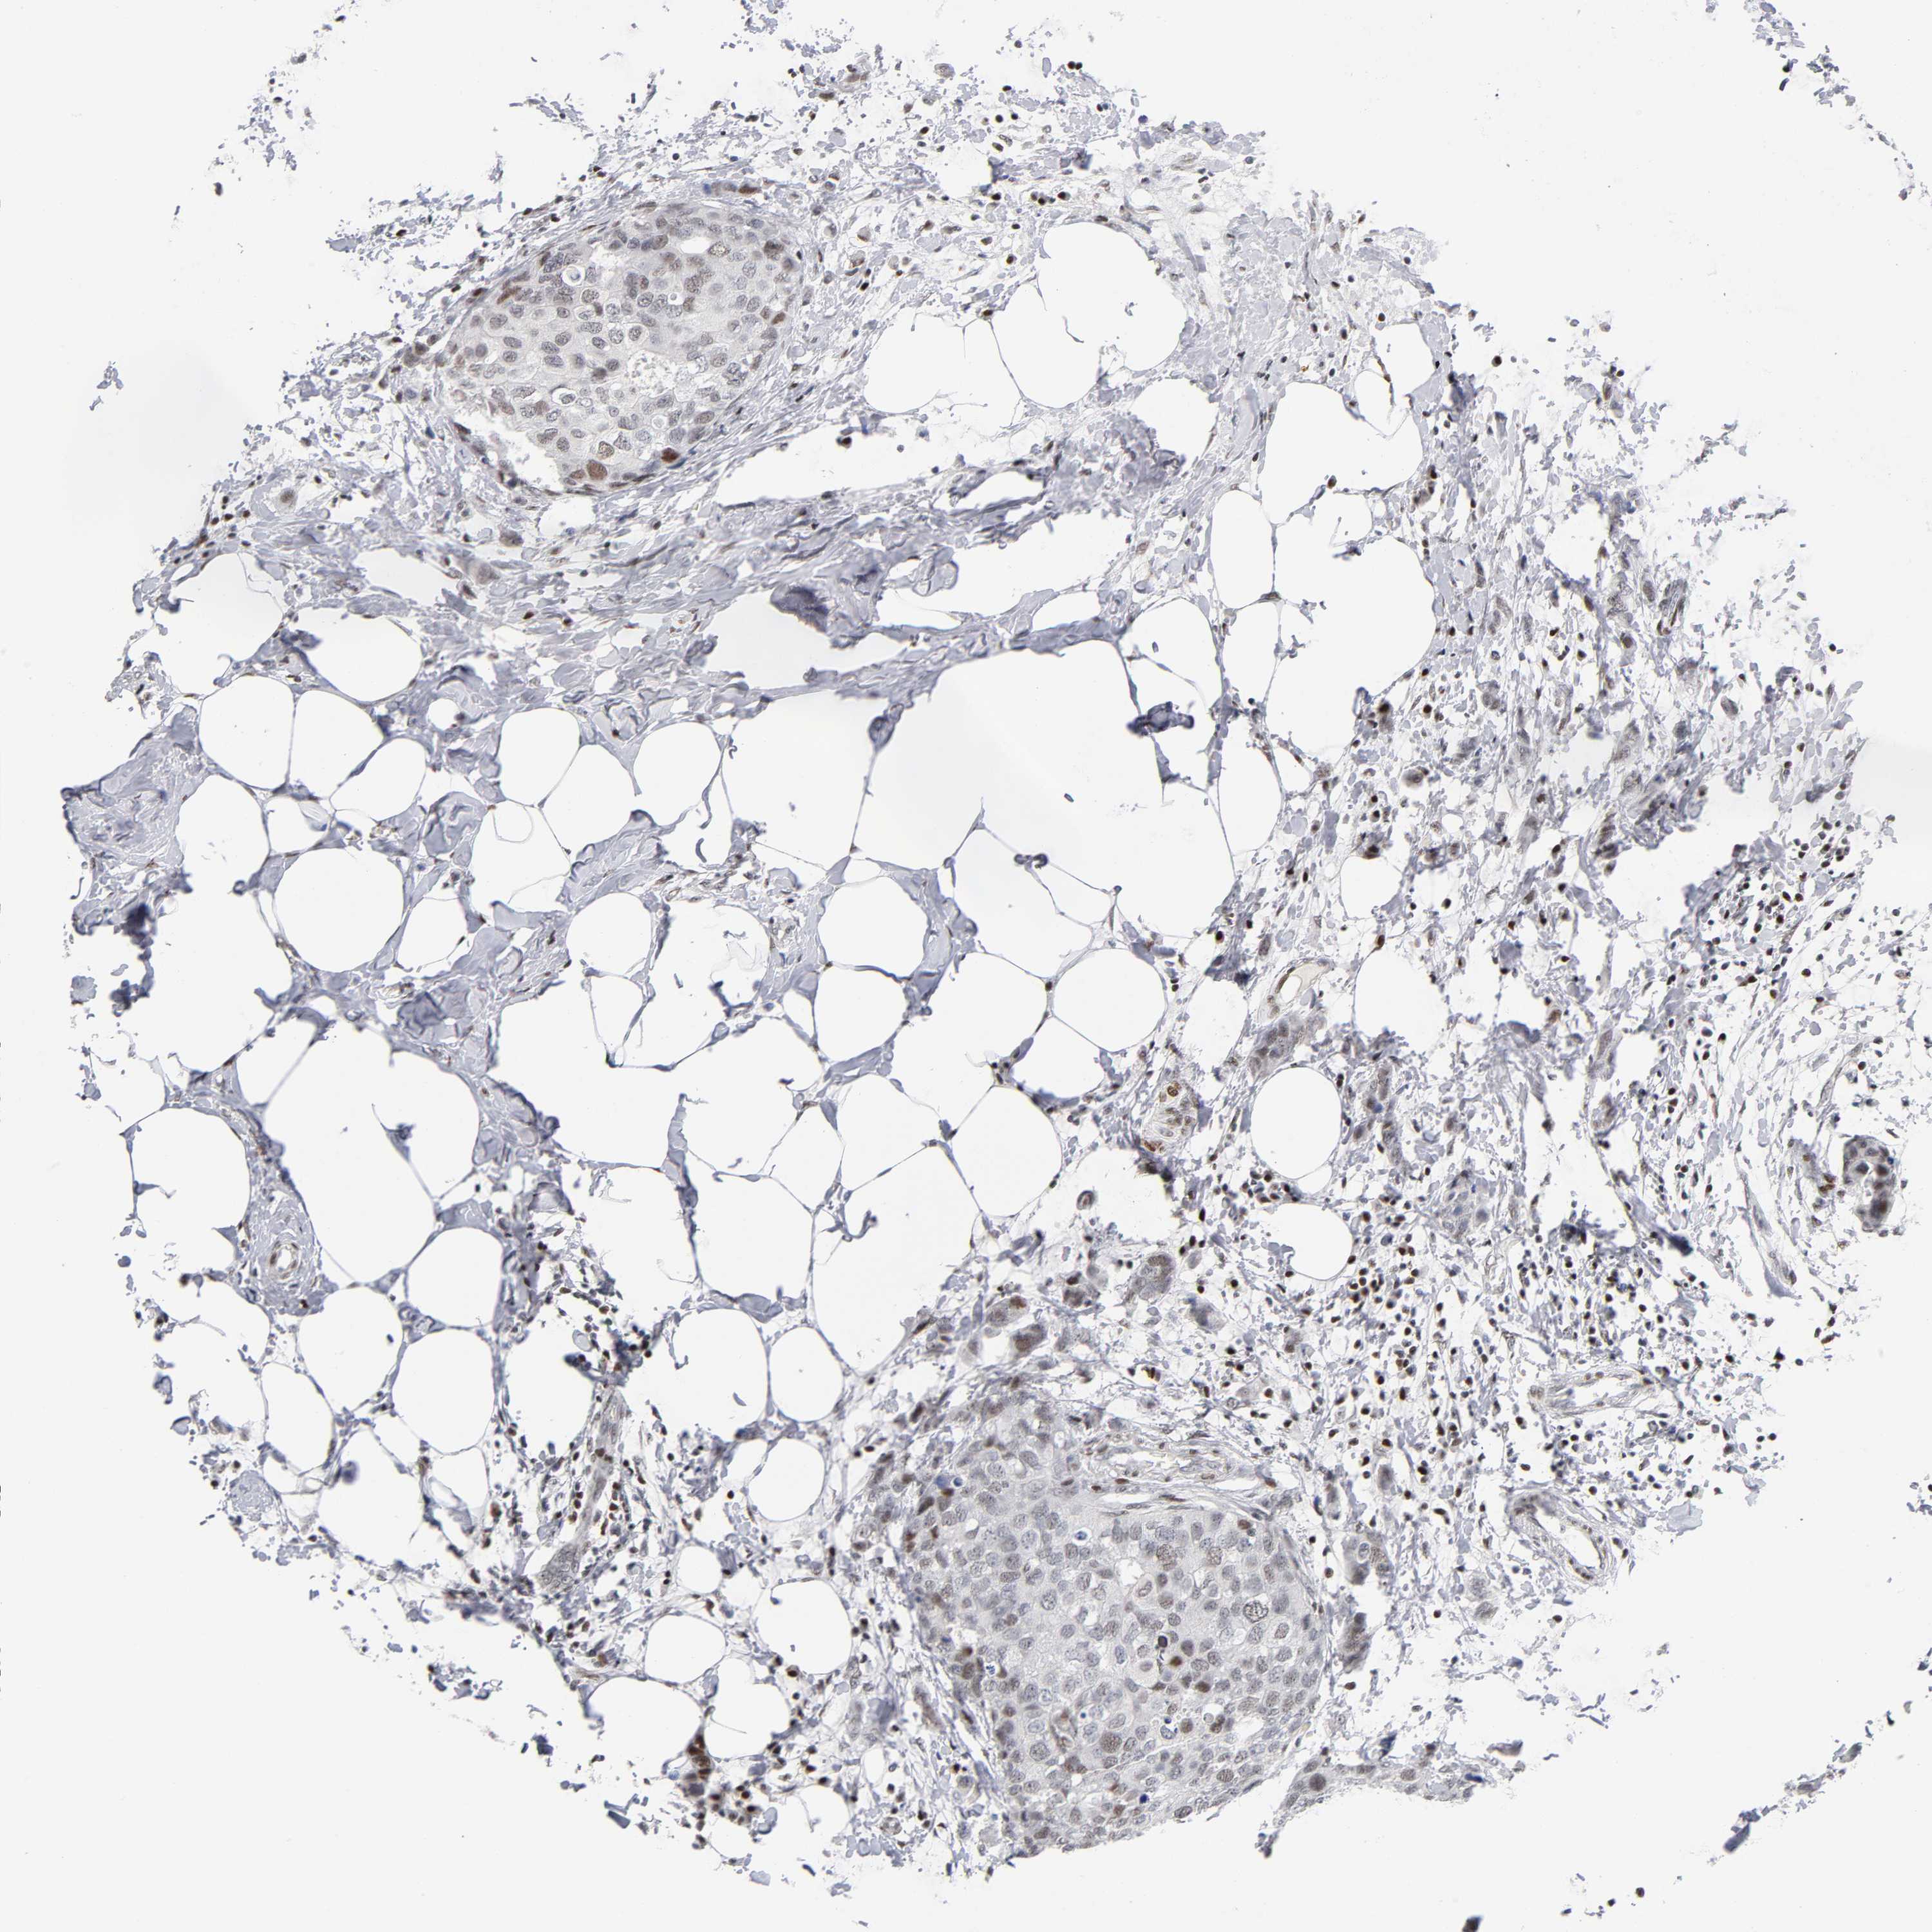

CANCER BREAST CANCER Show tissue menu

BRCA TCGA BRCA VALIDATION PROTEIN EXPRESSION

ANTIBODIES

AND

VALIDATION